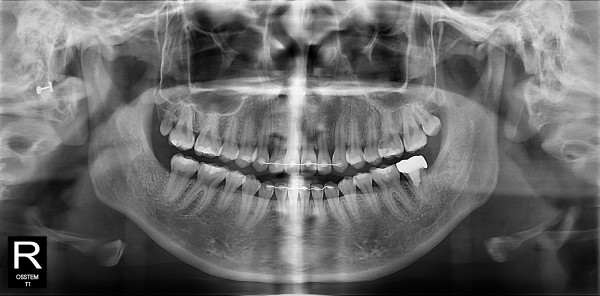

사랑니발치 10대/여성

ae27575af29d49719312fde5a1f0cca6_1764401999_3547.jpg